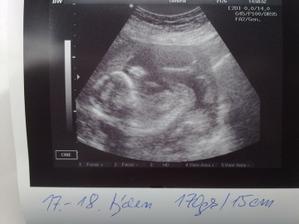

10.8.11 utz u MUDr.Vebery, vsechno v poradku, Emicka ma cca 15cm a 170g. Potvrzena holcicka;)